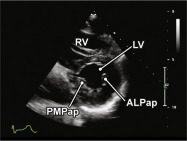

| 2.12. Mặt cắt trục ngắn cạnh ức (ngang mức các cơ nhú) |

||||||||

|

|

Cửa sổ siêu âm cạnh ức Mặt cắt trục ngắn cạnh ức Từ vị trí van hai lá gập đầu dò xuống dưới |

Thất phải (RV)

Vách liên thất (IVS) Cơ nhú sau giữa (PMPap) Cơ nhú trước bên (ALPap) Thất trái (LV) |

|||||